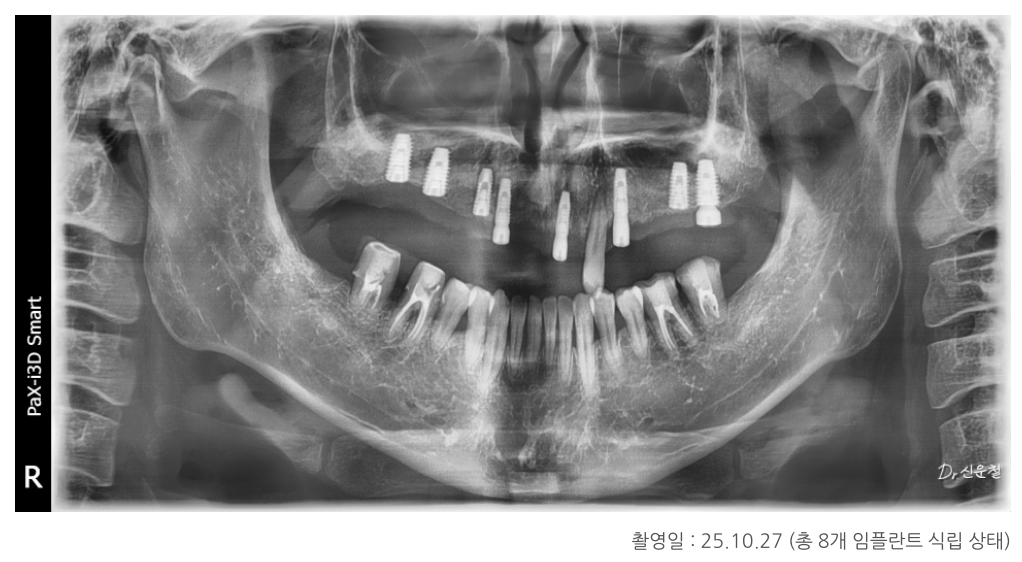

위턱·아래턱 상태 정밀 진단

위턱

남아 있는 치아 중 좌측 견치 1개만 보존 가능

견치는 뿌리가 길어 치조골 지지력이 비교적 좋은 치아

그 외 치아는 염증이 심하고 치조골 지지가 어려운 상태

아래턱

사랑니 발치 필요

양측 어금니는 신경치료 후 보철 치료가 불가피한 상태